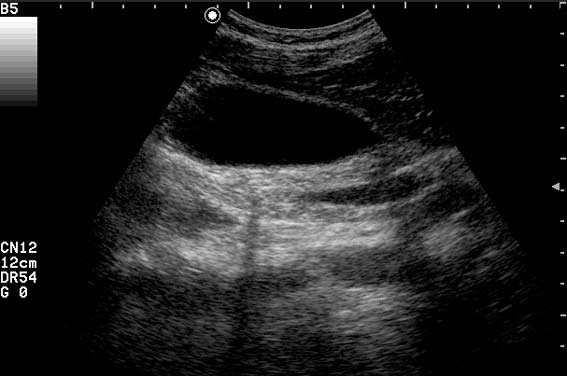

Пациент с приступом резких болей в животе, тошнотой, рвотой.

"Горошек" в пузыре и холедохе.

Да, ЖКБ, ходедохолитиаз, холецистолитиаз